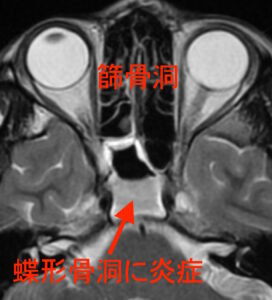

MRI検査で見たところ、

篩骨洞炎

蝶形骨洞という部分に液体が貯まって白くなっています。感染を起こして膿が貯まっている状態で、急性副鼻腔炎と診断しました。

この症例のような蝶形骨洞の副鼻腔炎は奥深い場所のため、レントゲン検査では分かりにくい事があります。